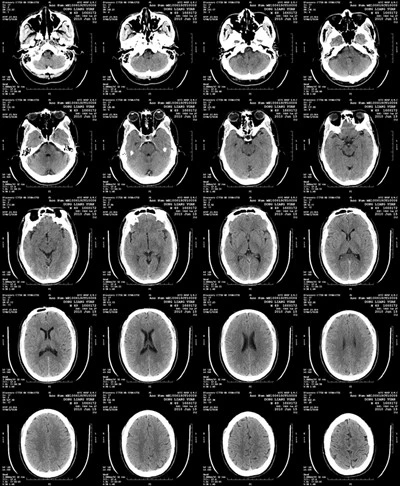

80世紀(jì),德國(guó)科學(xué)家W. C .倫琴發(fā)現(xiàn)了X射線,并拍攝了X射線片。次年,x光開始在醫(yī)學(xué)臨床上使用。此后,利用X線影像診斷原理,醫(yī)用激光膠片逐漸發(fā)展成為醫(yī)學(xué)領(lǐng)域一門獨(dú)立的放射技術(shù)學(xué)科。自20世紀(jì)70年代以來,由于計(jì)算機(jī)、激光、超聲和磁共振技術(shù)在醫(yī)學(xué)上的發(fā)展和應(yīng)用,放射診斷學(xué)已經(jīng)發(fā)展成為影像診斷學(xué)。

醫(yī)用激光膠片,到目前為止,銀鹽是一百多年來發(fā)現(xiàn)的不可替代的照相材料,科學(xué)家們還沒有找到比銀鹽更好的替代品。因此,無論在國(guó)內(nèi)外,醫(yī)用激光膠片都被公認(rèn)為是醫(yī)學(xué)圖像打印和圖像存儲(chǔ)的較好介質(zhì),是全球診斷圖像輸出的選擇。